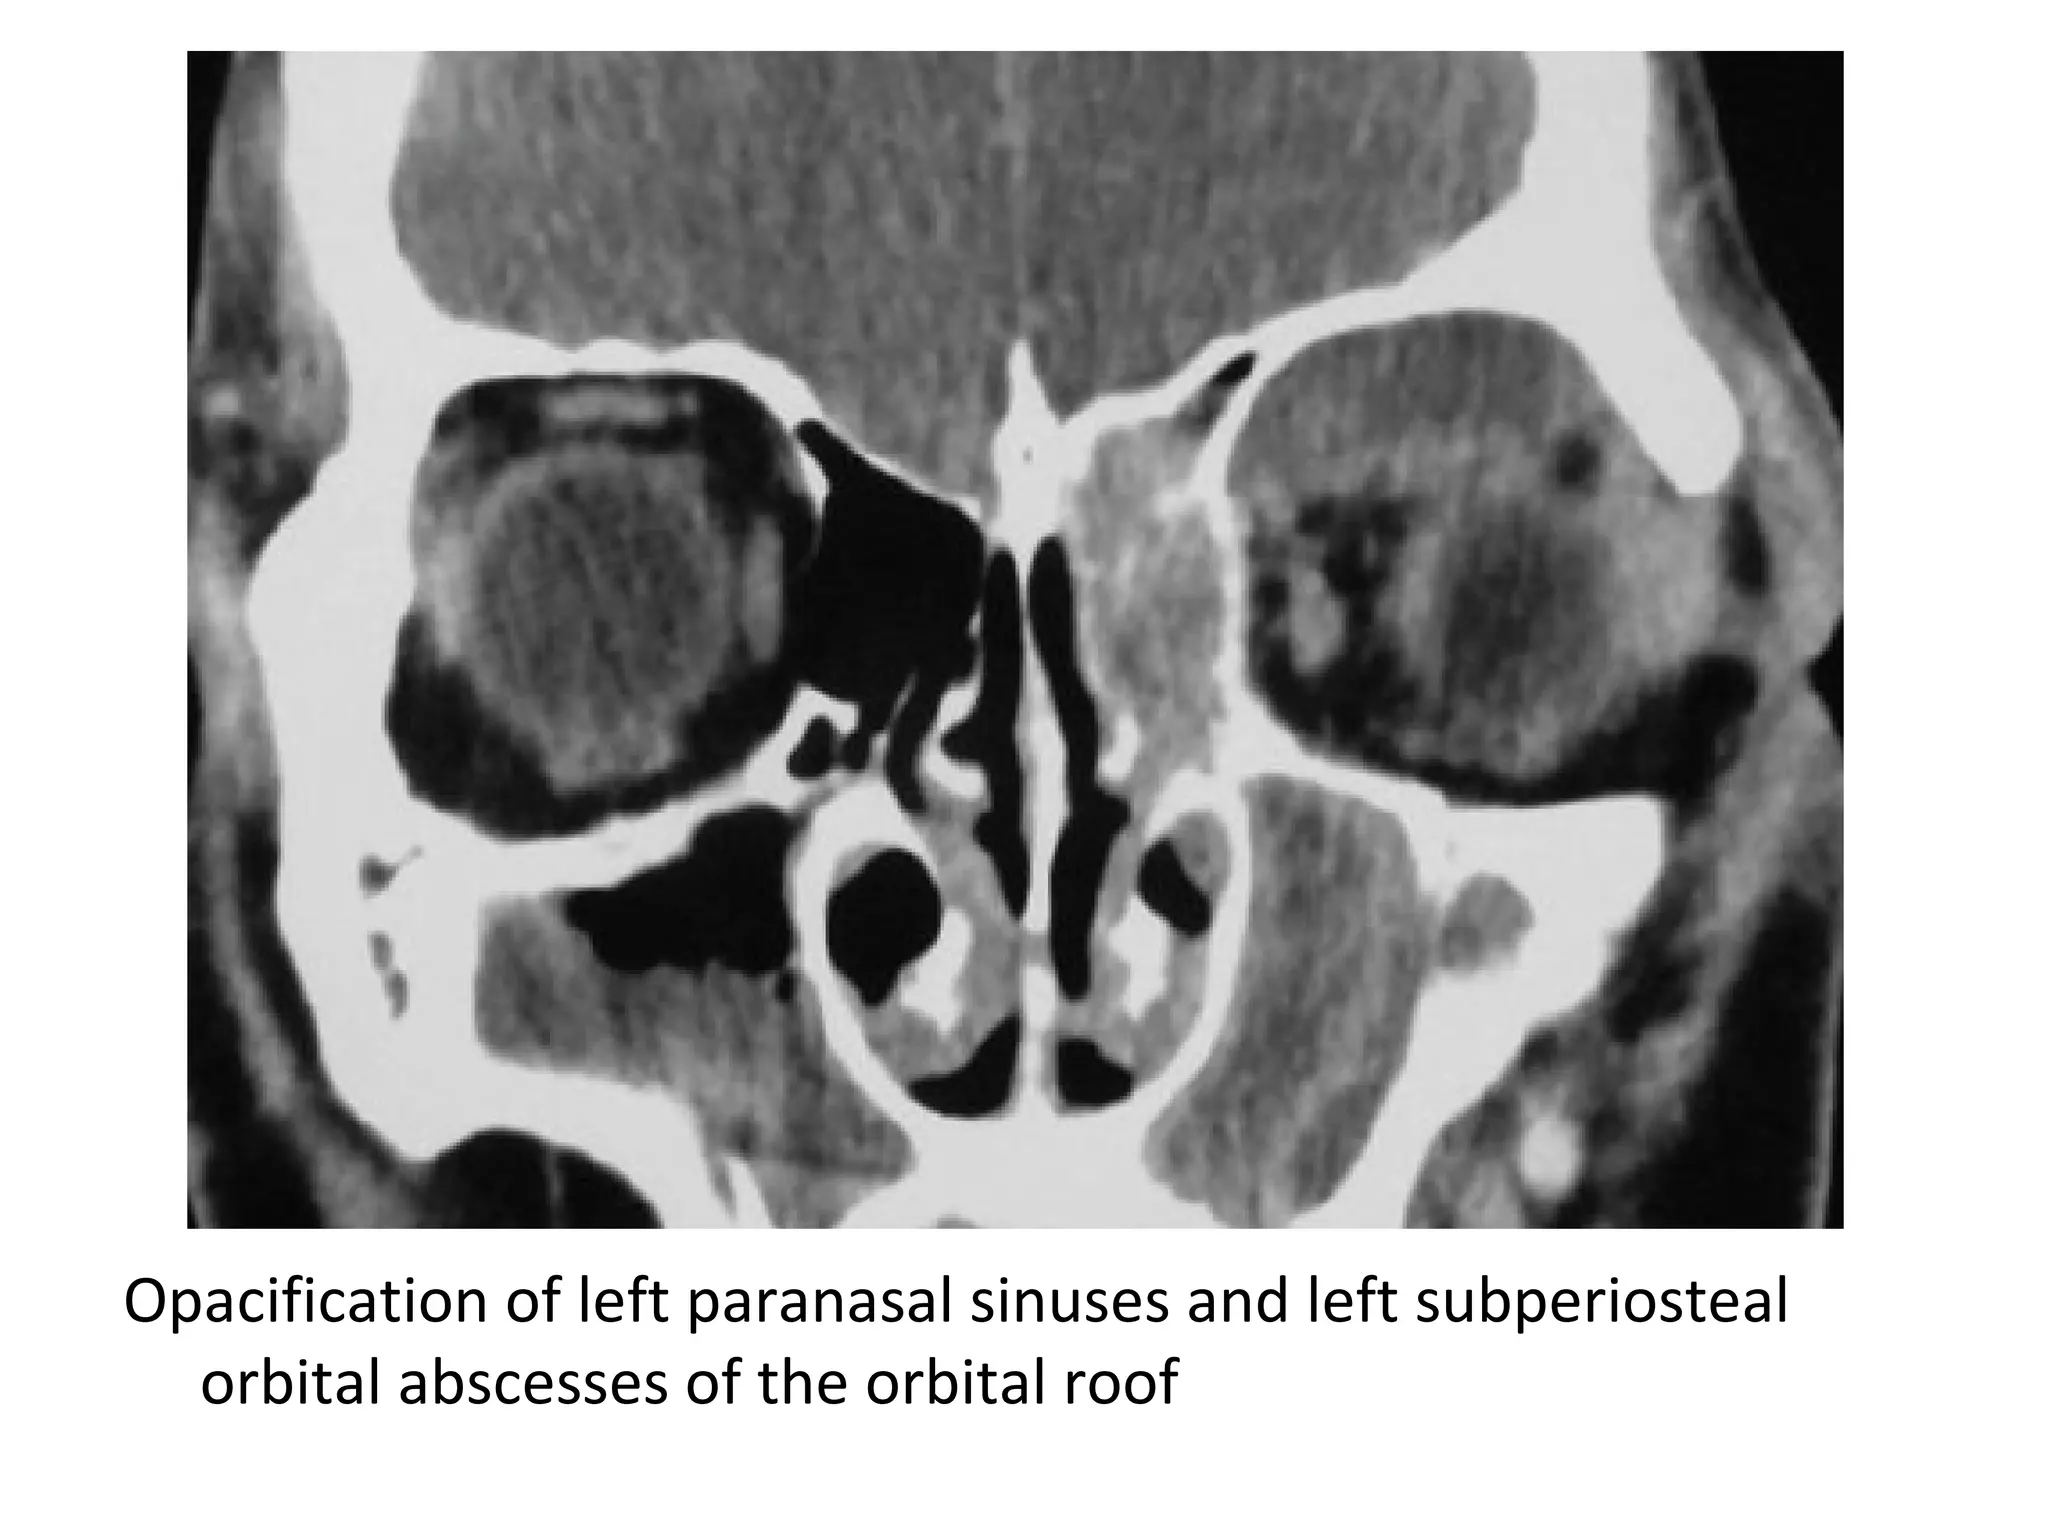

Opacification of left paranasal sinuses and left subperiosteal

orbital abscesses of the orbital roof